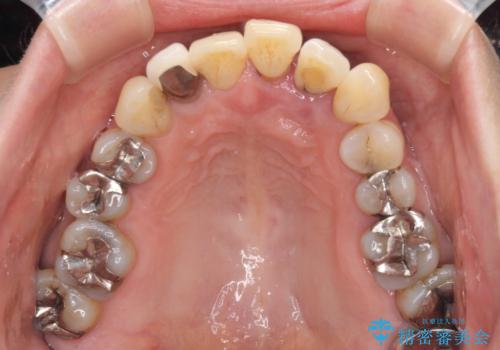

前歯のみならず、奥歯の銀歯や下顎前歯のデコボコなど、色々と気になる部分を治したいとのことでした。

前歯は抜歯が必要であったので、抜歯を行い、その後歯肉移植をおこなった上でオールセラミックブリッジによる補綴治療を行うこととしました。

下顎と上顎臼歯部については矯正治療を行い、奥歯の欠損部位はオールセラミックブリッジを、その他の銀歯はセラミックインレーなどにより治療を行うこととしました。